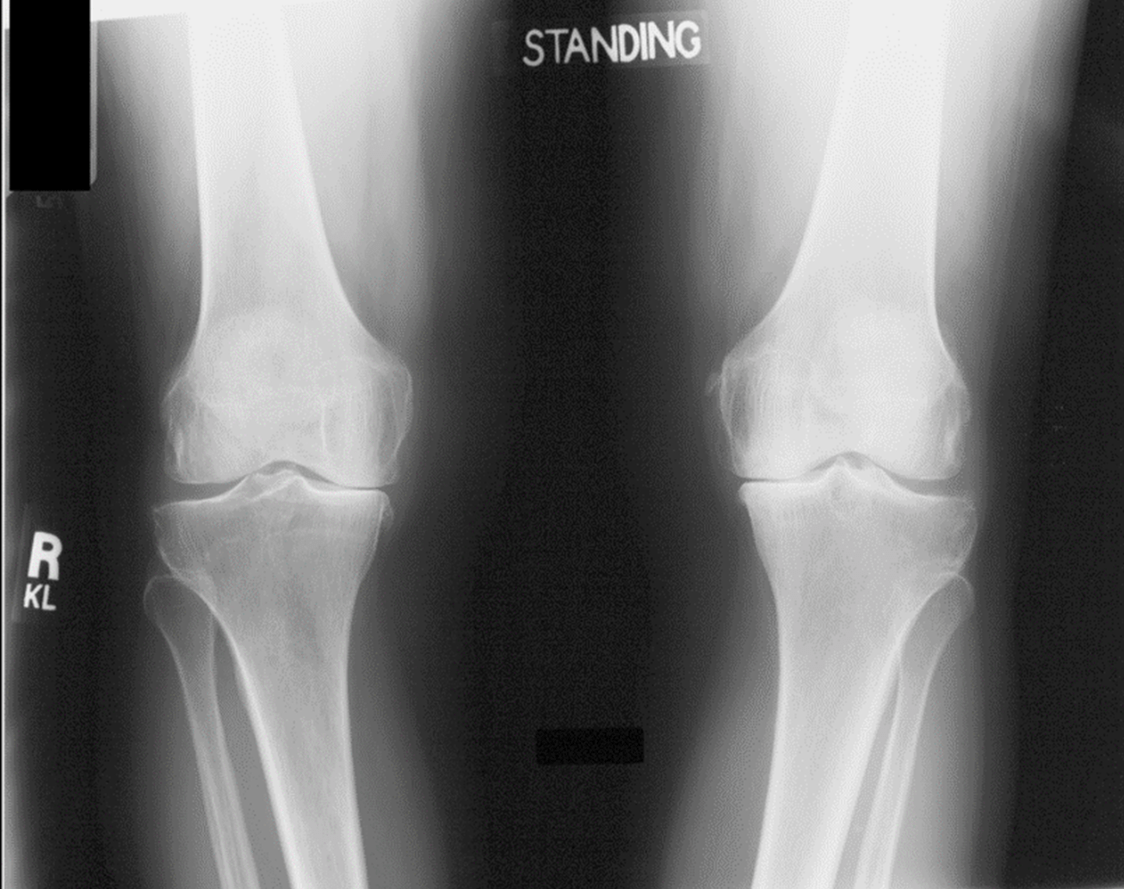

Which deformity is shown in X- ray?

Varus

Excessive genu varum alignment increases compressive loading on this compartment of the knee, accelerating osteoarthritic changes

Medial Compartment

This angle measured on a weight - bearing AP Knee X-ray, helps evaluate Varus or Valgus malalignment and guides surgical correction in osteotomies

Hip-Knee-Ankle Angle